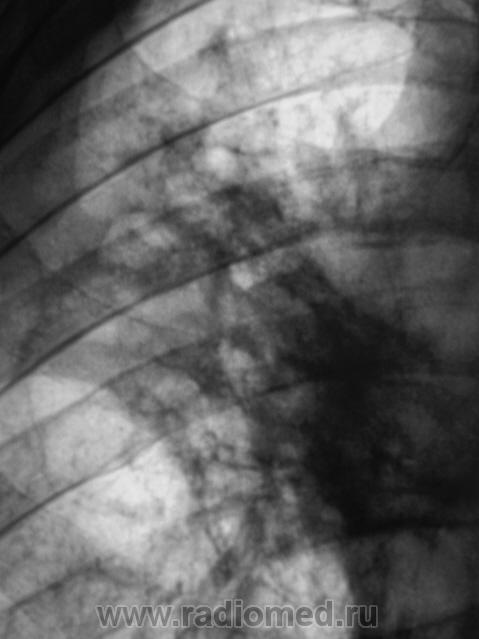

В туб. больнице, в процессе лечения произведена дополнительная томография.